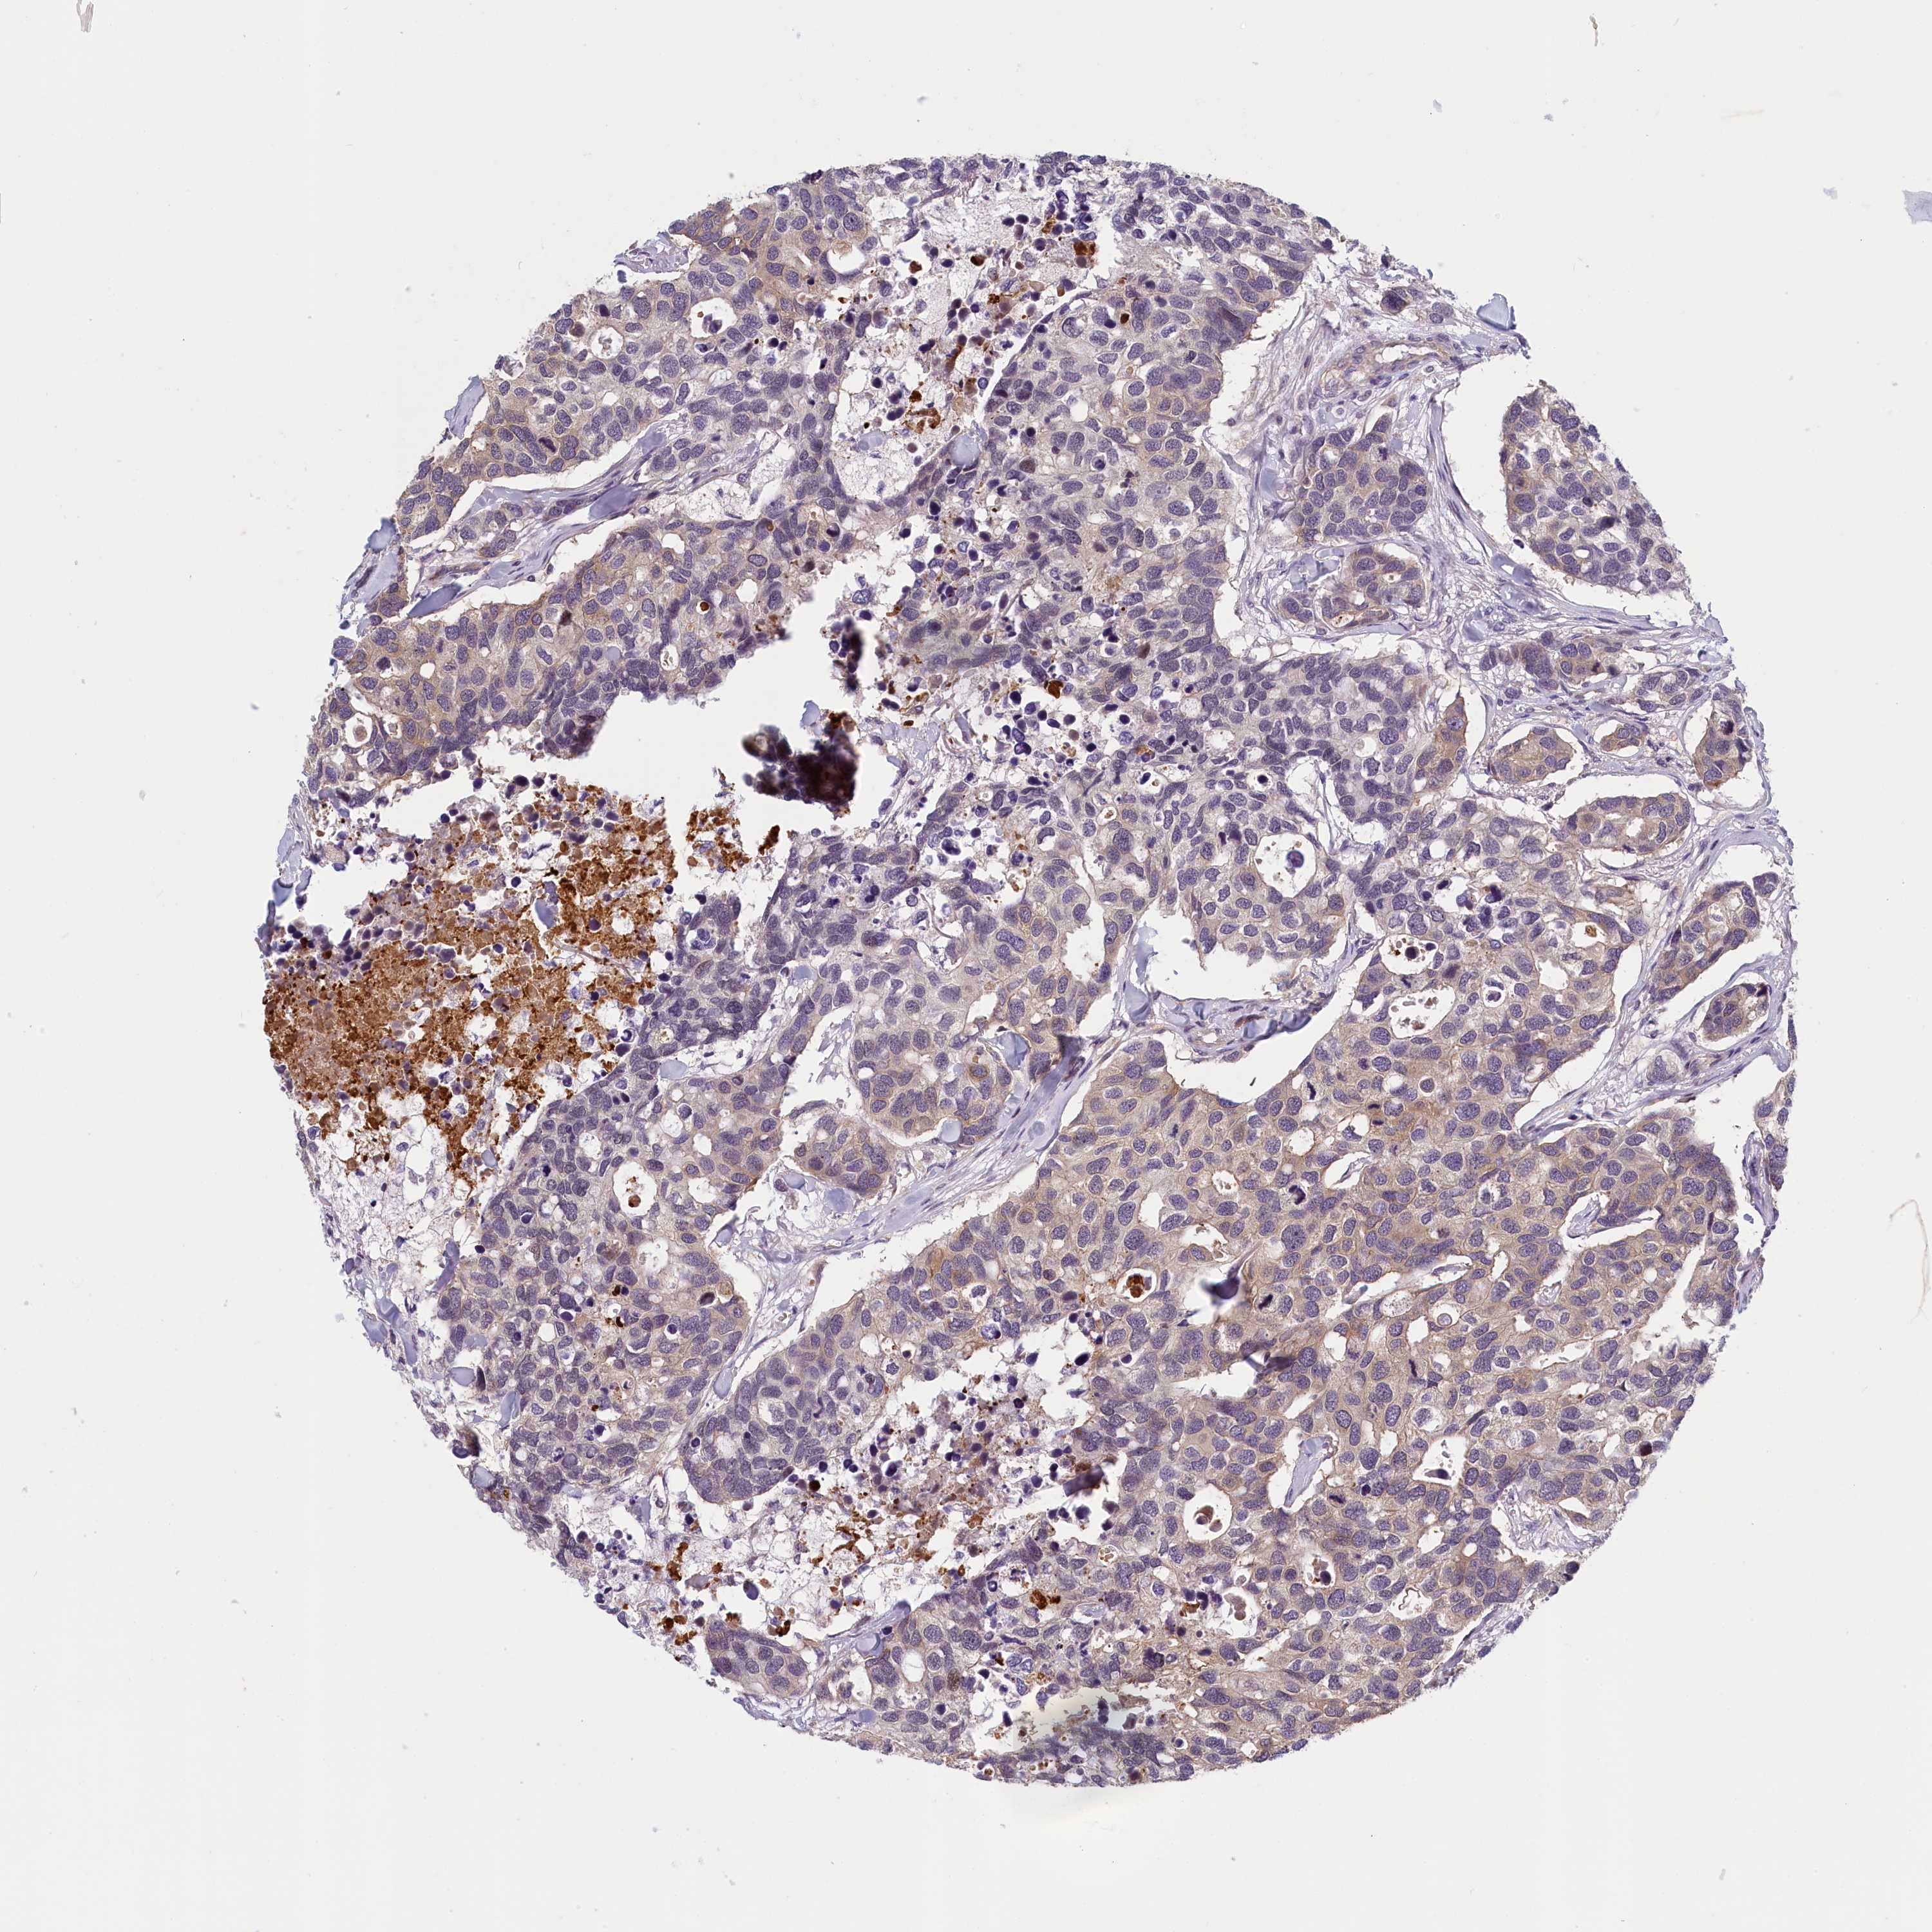

CANCER BREAST CANCER Show tissue menu

Breast cancer

Human cancer